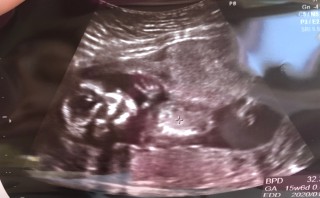

• おなまえみゆき

• ねんれい43

• 妊娠週15w6d

3月に流産してから、また妊娠でここまでやっと来ました。 大丈夫かなって、まだまだ先の心配あります‥がここまで来れました。 みなさんと比べると‥、ちょっと成長が遅い気がしてなりません。